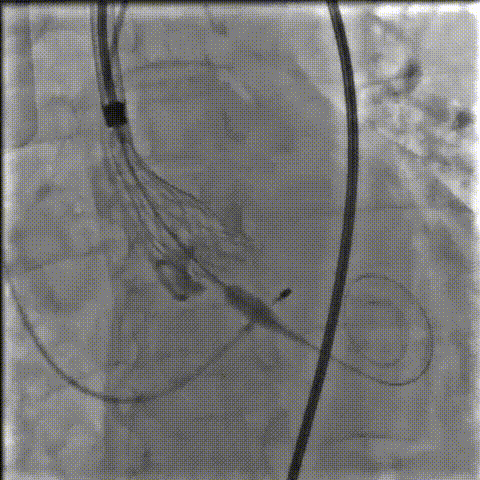

手术影像记录

主动脉根部造影

18mm球囊预扩

AV26瓣膜工作位造影

缓慢脱钩

23mm球囊后扩

后扩后造影:无漏

术中剪影